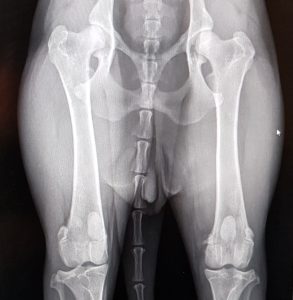

Endnu 2 hunde er blevet bedømt af DKK og fundet HD, AD og OCD frie, vi er så glade og stolte!